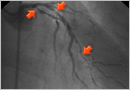

협심증

심장에 발생하는 협심증과 심근경색증, 뇌에 발생하는 뇌경색, 뇌출혈 등은 모두 혈관의 동맥경화와 원활한 혈관의 혈압 및 혈류 조절기능이 떨어져서 발생합니다. 심장은 온 몸에 혈액을 순환시키는 펌프역할을 하는 장기입니다. 이러한 심장의 운동에 의해 혈액이 전신을 순환하면서 산소와 영양분을 공급하고 이산화탄소와 노폐물을 실어 오는 것입니다. 한편, 심장 주위에는 관상동맥이라고 하는 특수한 혈관이 둘러싸고 있습니다. 관상동맥은 머리에 쓰는 왕관(王冠)처럼 심장 주위를 둘러싸고 있기 때문에 붙여진 이름이며 심장에 산소와영양분을

급성 심근경색증

급성 심근경색증이란 심장의 근육에 혈액을 공급하는 관상동맥이 여러 가지 원인에 의해 갑자기 막혀서 심근에 괴사(썩음)가 일어나는 질환입니다.